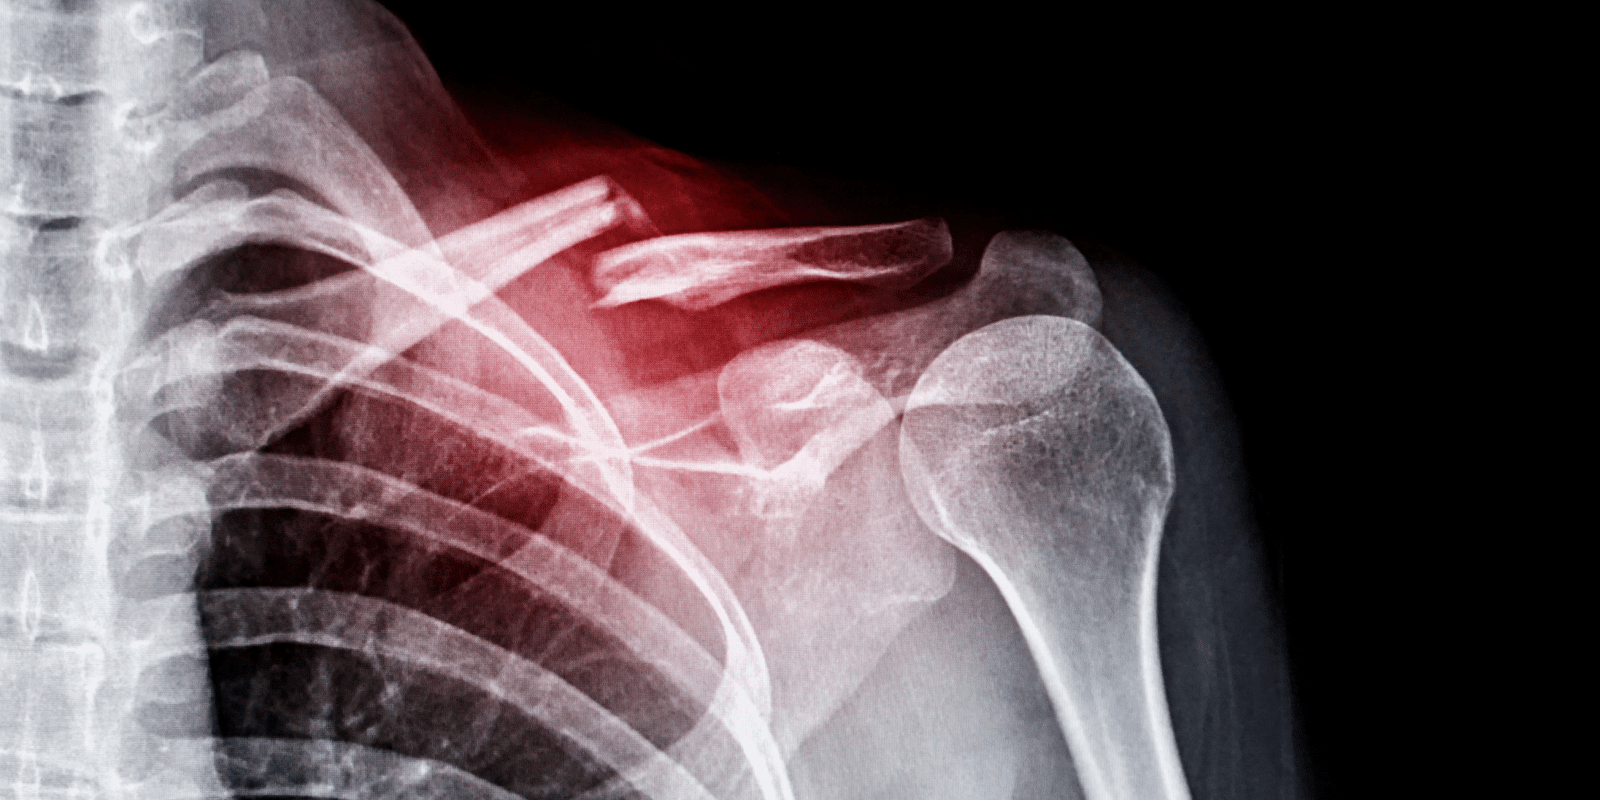

도수치료와 비용

도수치료는 손으로 직접 근육과 관절을 조작하여 통증을 줄이고 기능을 향상시키는 치료 방법입니다. 이는 골절 후 재활 과정에서 중요한 부분을 차지하며, 환자의 회복 속도와 통증 정도에 따라 치료 계획이 조정될 수 있습니다. 도수치료 비용은 치료의 빈도와 세션의 길이, 필요한 치료의 종류에 따라 달라지며, 실비보험을 통해 일부 비용을 보장받을 수 있습니다.